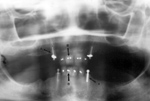

| Panoramic view of the mandible shows dental plates with screws (A) and bone ligature wires (B). There are multiple dental alloy restorations (amalgam fillings). From Harkins, 1994 |